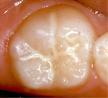

シーラント前              シーラントをした状態